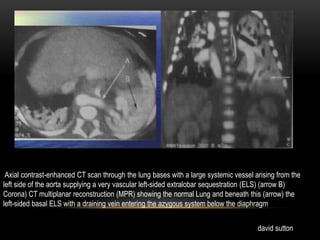

Axial contrast-enhanced CT scan through the lung bases with a large systemic vessel arising from the

left side of the aorta supplying a very vascular left-sided extralobar sequestration (ELS) (arrow B)

Corona) CT multiplanar reconstruction (MPR) showing the normal Lung and beneath this (arrow) the

left-sided basal ELS with a draining vein entering the azygous system below the diaphragm